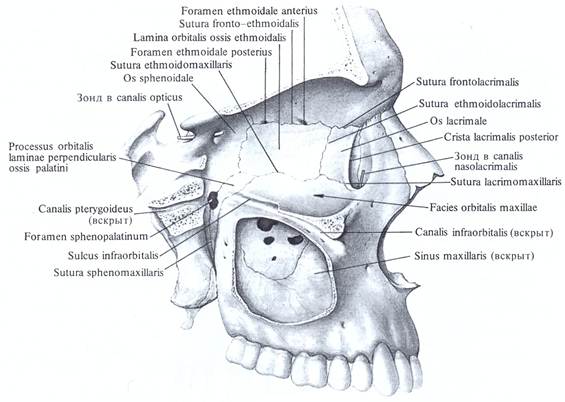

Анатомические особенности: фотографии ямок черепа, височной и подвисочной крылонебной